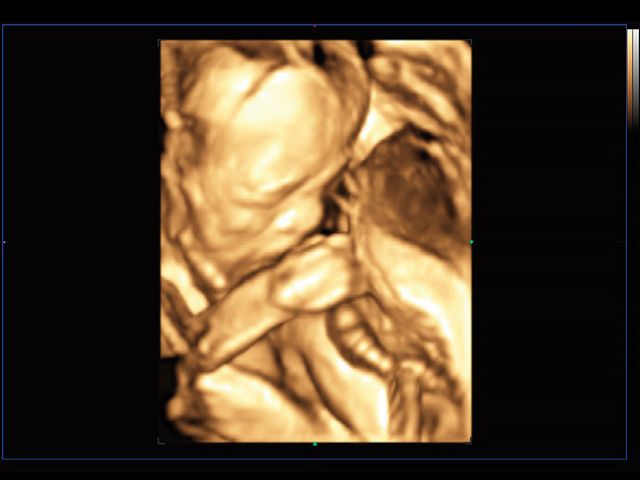

RealisticVue™ displays high resolution 3D anatomy with exceptional detail and realistic depth perception. User selectable light source direction creates intricately graduated shadows for better defined anatomical structures.